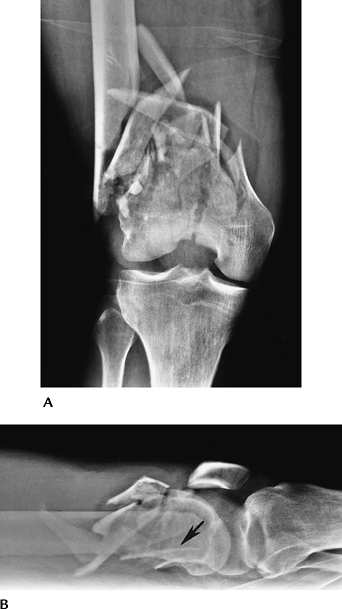

Skeletal Trauma: Proximal Tibial Fractures

Key Facts

Proximal tibial fractures may be extra-articular or articular (tibial plateau or condylar fractures).

Tibial plateau (condyle) fractures

account for 1% of all fractures and 8% of fractures in the elderly. The

majority (55%–70%) of plateau fractures involve the lateral plateau.

Isolated medial plateau factures occur in 10% to 23% of cases, and

medial and lateral fractures occur in 10% to 30% of cases. -

Mechanism of injury is motor vehicle

accidents (54%) or falls (46%) leading to vertical compression (T and Y

fractures) varus and valgus forces (medial and lateral plateau

fractures, respectively). -

Ligament and meniscal injuries are common with varus, valgus, or twisting forces.

AP and lateral radiographs usually are diagnostic for displaced fractures.

CT and MRI frequently are indicated to evaluate fragment position and soft tissue injury.

Management is based on four key factors:

degree of articular depression, degree of fragment separation, degree

of comminution, and extent of soft tissue injury. -

Depression of 4 to 8 mm and separation of fragments 4 mm or more generally indicate a need for internal fixation.

Complications include infection, nonunion, and arthropathy.

Ipsilateral, femoral, and tibial condylar fractures are not uncommon and have the following significant associated injuries:

-

Abdominal and chest injuries 20%

Open injury to leg 60%

Neurovascular injury 7%

![]() |

FIGURE 5-8

Hohl classification of tibial plateau fractures: I, undisplaced fracture (24%); II, central depression (26%); III, split compression, usually with fibular fracture (29%); IV, total condylar depression (11%); V, comminuted bicondylar fractures (10%). |

P.222

FIGURE 5-9 (A) Tibial plateau fracture with splitting and separation laterally. (B) Tibial plateau fracture reduced with buttress plate and screws to restore joint congruency.